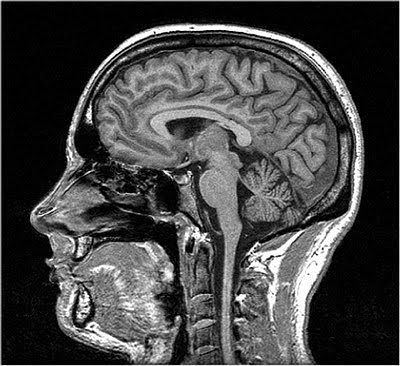

Takes advantage of the magnetic properties of hydrogen, specifically protons in the hydrogen atom.

Used for structural images of the brain.

Excellent spatial resolution.